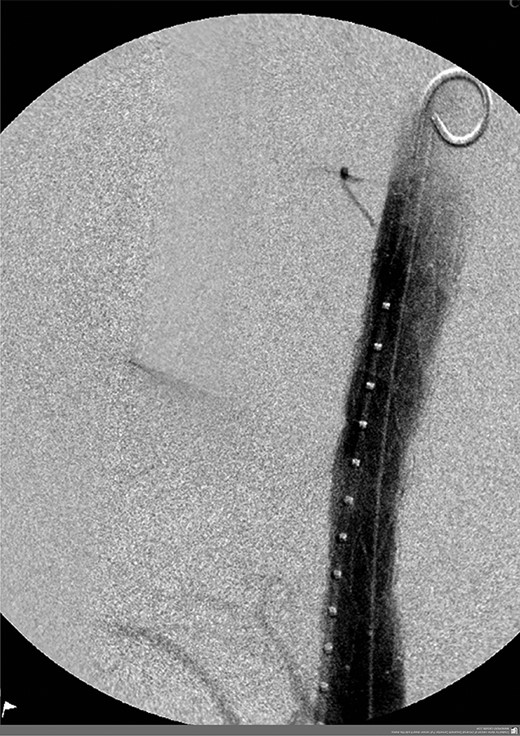

A 57-year-old male presented haemodynamically unstable with a blood pressure of 85/50 mmHg and a heart rate of 136 bpm with haematemesis, melaena and 4-day history of back pain. Fifteen years previously he was treated for a poorly differentiated adenocarcinoma (pT3 pN1 MX) close to the gastro-oesophageal junction with chemotherapy and trans-hiatal oesophagectomy. He received no radiotherapy. Apart from being a life-long smoker he had no other positive social risk factors or medical history. He underwent immediate oesophago-gastro-duodenoscopy (OGD). This showed fresh and clotted blood in the gastric remnant but no bleeding source was identified. He had a pulseless arrest during the OGD but underwent successful cardiopulmonary resuscitation. Following this a CT angiogram was performed. This demonstrated a fistula between the neo-oesphagus and the thoracic aorta (Fig. 1). Following discussion between an upper gastro-intestinal surgeon, a vascular surgeon and an interventional radiologist the patient was taken to the operating theatre. Under general anaesthesia an initial thoracic aortogram was performed from the right groin to confirm the presence and location of the AGF (Fig. 2). Following this, a covered thoracic stent graft (Cook Medical ZTA-24-105/diameter of 24 mm and length of 105 mm), was inserted via the femoral artery under image guidance. The stent graft, usually used in aneurysmal repair, was placed in the thoracic aorta across the fistula and occluded it. Subsequent angiogram showed no leak (Fig. 3). The patient became haemodynamically stable and had an uneventful recovery.

CT angiogram showing aorta-enteric fistula demonstrated by arrow (axial and sagittal view, respectively).